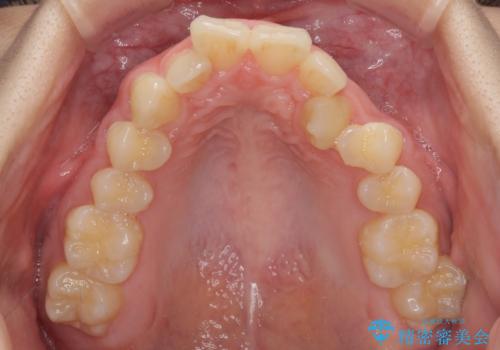

- 咬み合わせが悪いとのことで来院された患者様です。

ぱっと見はインビザラインによる矯正治療も可能と思われましたが、歯根が最も長い犬歯がクロスバイトになっており、インビザラインでは対応困難と判断され、ワイヤー装置にて矯正治療を行うこととしました。